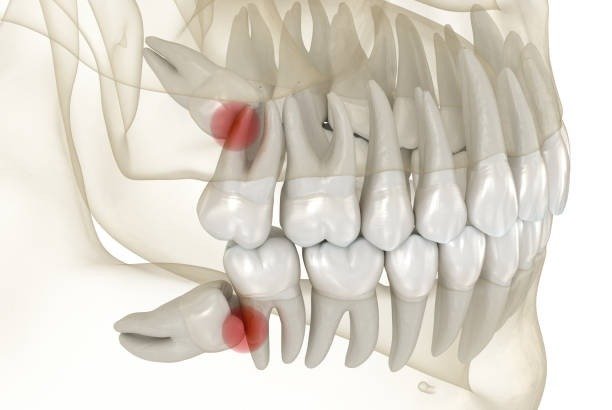

Wise are extracted through an operation, that is through a surgical process, where the tissues of the mouth and often the bone have to be cut. Consequently, the recovery process is important to minimize incidences such as infection or dry socket, which is a painful condition whereby the clot formed in the tooth socket is dislodged, thereby, releasing the nerves and bones seated at the bottom of the socket.

Some of the several consequences you can experience if you do not adhere to the directions your oral surgeon has given include the following: the frequent complication is the dry socket where the clot is removed and exposes the nerves and bones. Symptoms of dry socket include:

- Intense pain at the site of extraction

- Pain that goes to your ear or any terrific part s of the face

- Inability to use the extraction site for any activity or painful sensation whenever touching or using the site

- Visible bone in the socket

Dry socket could mean your oral surgeon have to pack the sockets with medicated gauze and may prescribe pain relievers. Some healing time will be prolonged and the pain can be severe sometimes.

Other risks are infection of the wound site, increased bleeding and slow healing. These problems tend to be more prevalent when vaping is done too soon after the surgery has been carried out and this is the reason why everyone should ensure that they follow these guidelines to the letter.